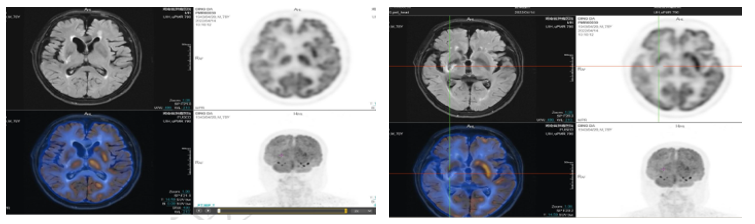

第3-8周期使用塞利尼索(40mg,QW)联合替雷利珠单抗(200mg)和奥布替尼(100mg,QD)方案治疗。治疗期间复查颅脑PET/MRI和全身PET/CT评估疗效:持续CR。

上图、中图:颅脑PET/MRI图